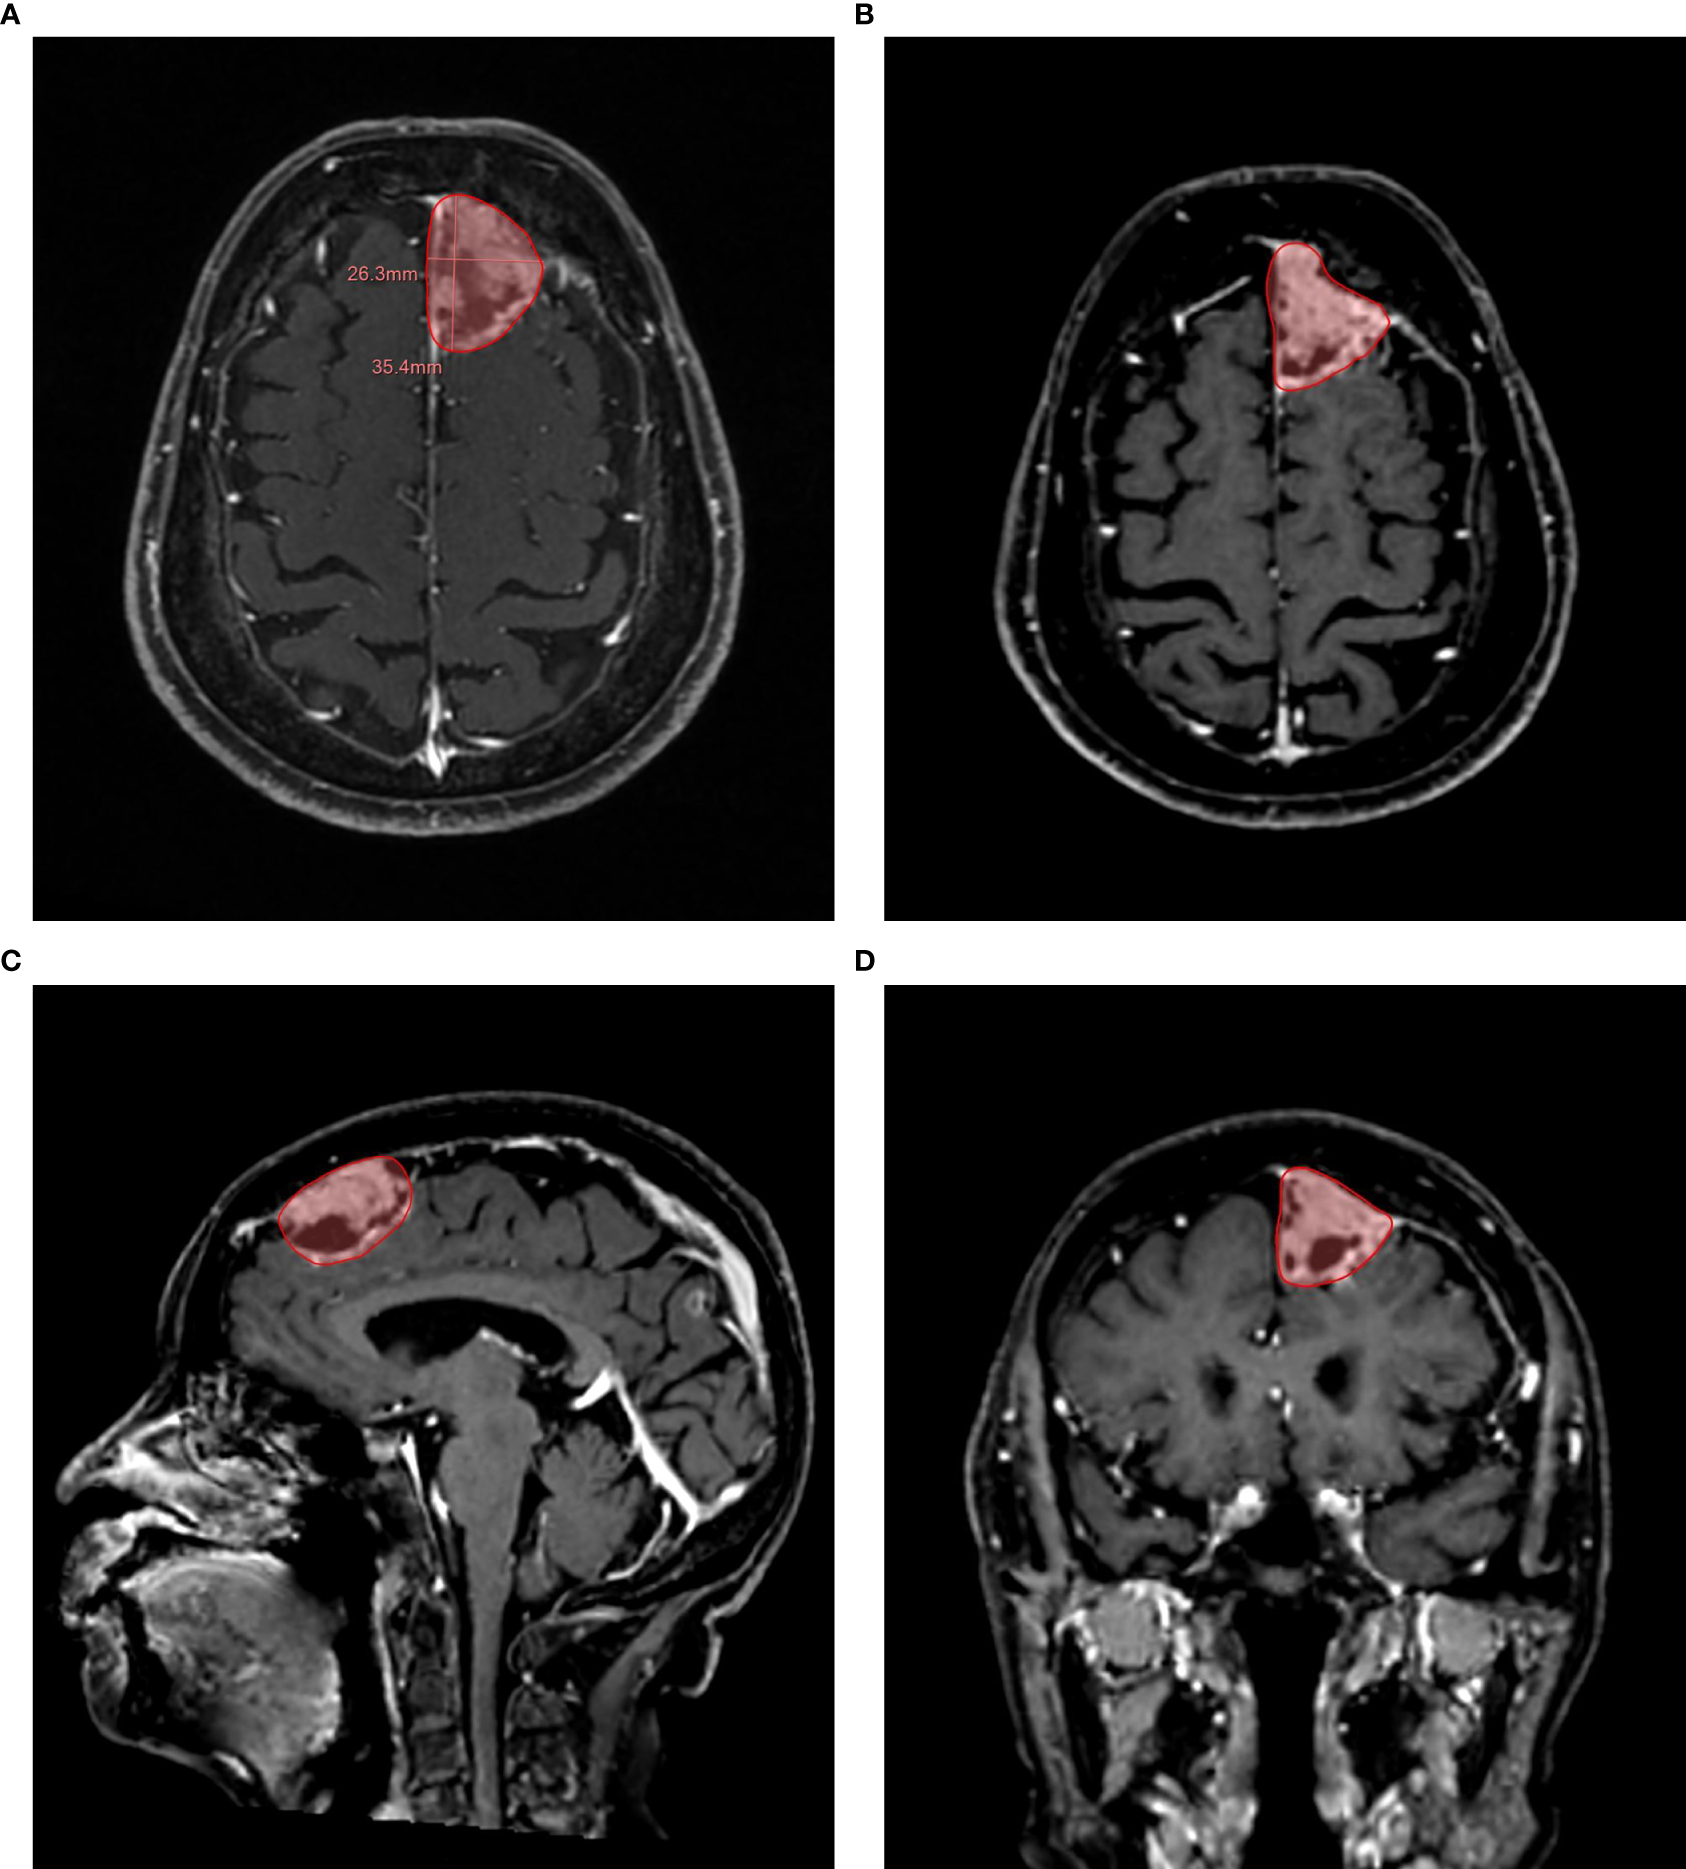

Figure 2

Example of a semi-automatic segmentation. The follow-up 3D CE-MRI of an 84-year-old female patient with brain metastases from lung adenocarcinoma. (A): Automatic measurement of maximum long diameter and maximum axial diameter. (B): Semi-automatic segmentation in axial plane. (C): Semi-automatic segmentation in sagittal plane. (D): Semi-automatic segmentation in coronal plane.